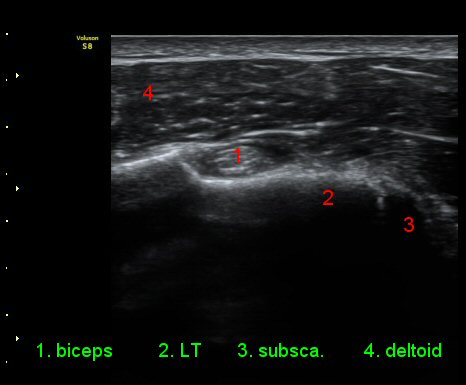

ÆÈÀ» ¿ÜȸÀüÇÏ´Ï °ß°©ÇÏ±Ù°Ç Ç¥ÃþÀÇ ¼ö¾×Àú·ù°¡ ´õ¿í È®½ÇÇÏ°Ô °üÂûµµ´Ï´Ù(»çÁø 4).